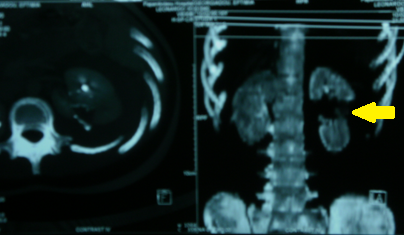

Αξονική τομογραφία οπισθοπεριτοναίου. Κίτρινα βέλη – Αμφοτερόπλευρη διάταση ουρητήρων. Ευγενική παραχώρηση Dr. V. Penopoulos.